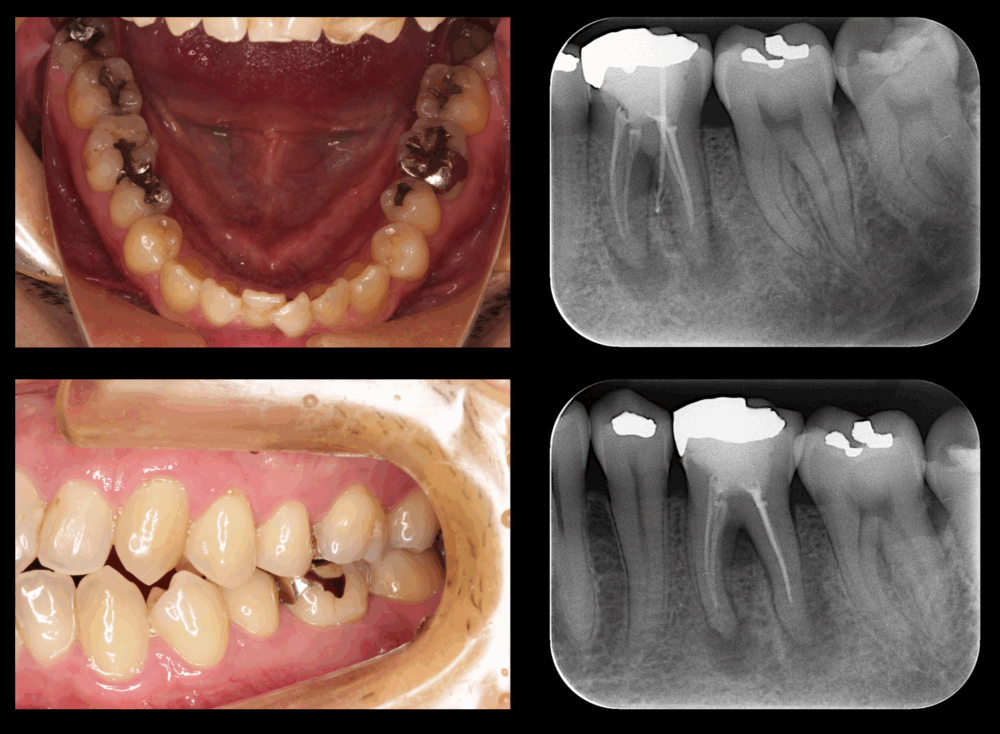

ももこ歯科のブログを読んでくださる皆様、いつもありがとうございます。 今回のケースは、サイナストラクトがあり、深い歯周ポケットが存在する歯内歯周病変です。前回までのケース:サイナストラクトがあり、浅い歯周ポケットが存在す...